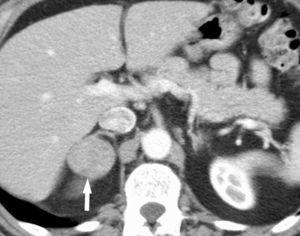

Metástasis hepáticas y suprarrenales

La aparición de nódulos suprarrenales se da en más del 10% de los pacientes con cáncer de pulmón. Dada la elevada frecuencia de adenomas benignos, es crucial la distinción entre éstos y la afectación metastásica. Ésta se puede llevar a cabo con una combinación de estrategias de imagen que incluyen TC, RM y/o PET. Por TC los adenomas suprarrenales típicamente tienen valores de atenuación bajos por la presencia de cúmulos lipídicos. Una lesión suprarrenal con valores de atenuación menores de 10 unidades Hounsfield (UH) en el estudio sin contraste, tiene una probabilidad del 98% de que se trate de una lesión benigna. Dado que ambas lesiones, adenomas y metástasis captan contraste, la valoración rutinaria de la captación no es útil en la diferenciación entre benignidad y malignidad. Si se detecta durante la realización de la TC, realizar cortes tardíos a los 15 minutos de la administración de contraste es importante, ya que si existe un lavado del contraste de más del 50% el diagnóstico de adenoma tiene una sensibilidad del 98% y una especificidad que oscila entre el 92 y el 100%20. La RM con secuencias de desplazamiento químico en la valoración de nódulos suprarrenales tiene una especificidad del 100% para el diagnóstico de adenoma (fig. 14). Sin embargo, la sensibilidad depende de la densidad de la lesión en el estudio con TC, ya que cuanto mayor es la densidad en la TC menos señal perderá en la RM, con lo que resulta más difícil etiquetarlo como adenoma21. La PET presenta una sensibilidad alta en la detección de metástasis suprarrenales, ya que cuando una lesión suprarrenal no muestra signos concluyentes en la TC de benignidad, la ausencia de actividad con la PET hace muy probable dicho diagnóstico. En los casos en que persistan dudas diagnósticas se debe recurrir a la biopsia de la lesión adrenal, especialmente si de este diagnóstico depende el manejo del paciente.